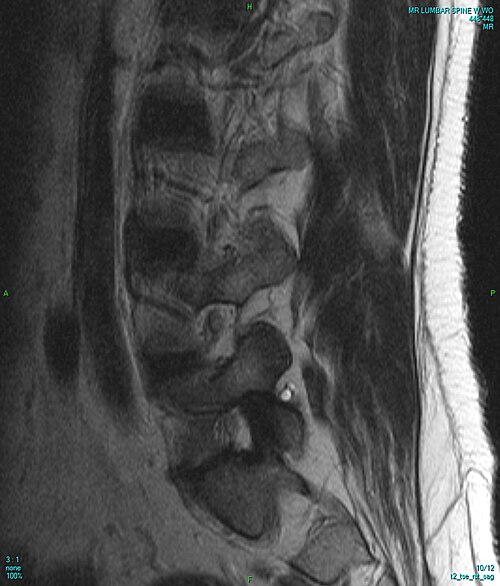

L4-L5 posterolateral disc herniation compressing the L5 nerve root with disc desiccation, annular tear, and...

Lumbar spinal stenosis with ligamentum flavum hypertrophy, facet joint arthropathy, disc bulge, and narrowed central canal